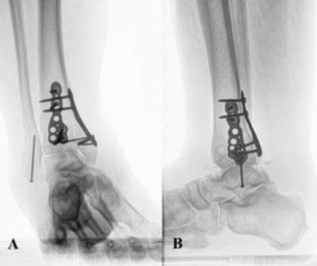

A 63-year-old man with right posttraumatic osteoarthritis was initially seen for constant ankle pain and paresthesia (Figure 1). The patient previously had a pilon fracture following a high-speed automobile accident. The fracture was repaired and fully healed with a posterior plate, medial plate, and screw fixation in the fibula (Figure 2). The patient adamantly declined undergoing AA because he wanted to maintain ankle mobility. Patient risk factors for poor peripheral circulation included a 10-pack-year smoking history, a body mass index of 37 kg/m2, and a medical history significant for chronic venous stasis, lymphedema, deep vein thrombosis, and hypertension. The listed risk factors caused him to be a poor surgical candidate, and TAA was relatively contraindicated. Additionally, on initial physical examination, he had visibly poor ankle integument, ankle hemosiderin deposits, and mild to moderate venous congestion.